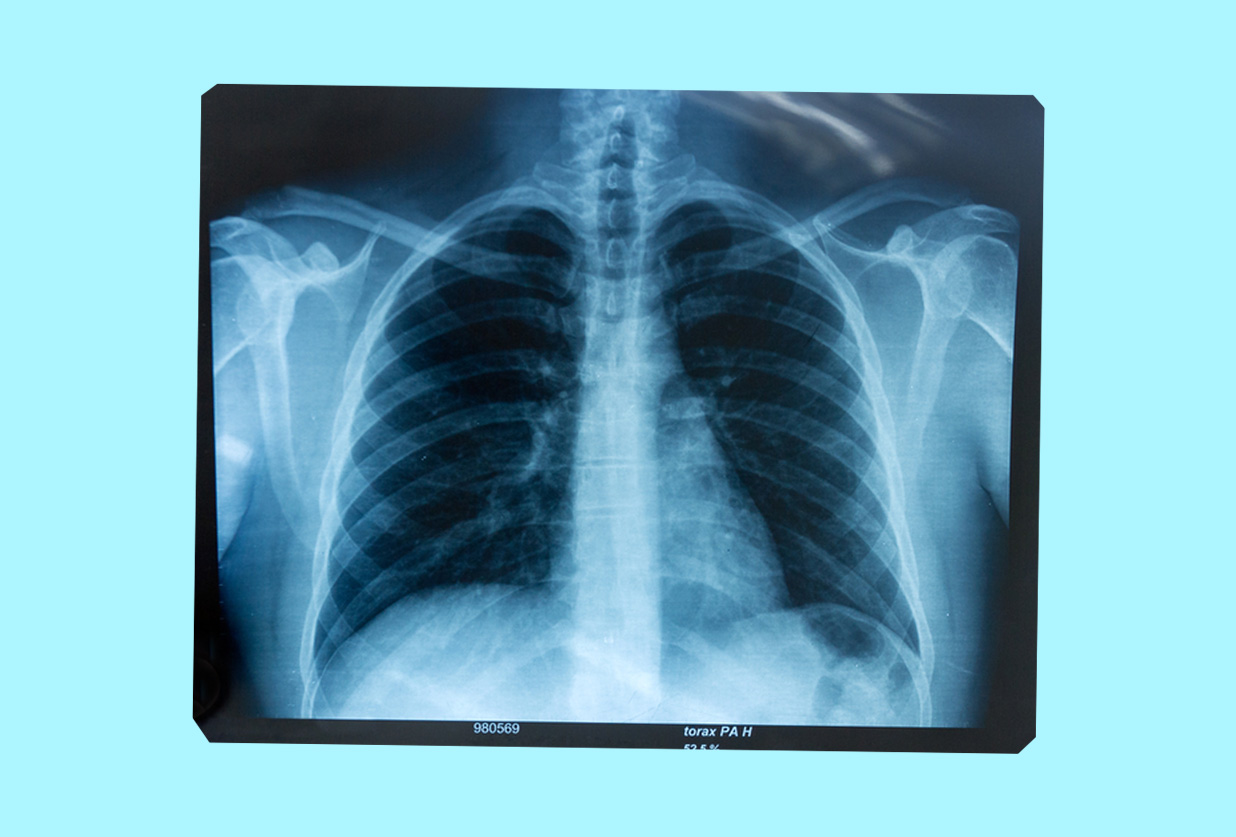

The basics normally include measuring height and weight (to keep track of BMI), taking blood pressure (high indicates a risk of heart disease, low can cause dizziness, fainting, etc.), and blood tests to check for diseases like anemia, infection, and cancer. Urinalysis (urine) tests detect kidney disease, diabetes etc.), electrocardiograms check heart rhythm, and chest x-rays can help pneumonia, heart failure, lung cancer, tuberculosis, sarcoidosis, and lung tissue scarring (fibrosis). These check-ups don't usually test for STIs though — find out more about how and where to do that here.